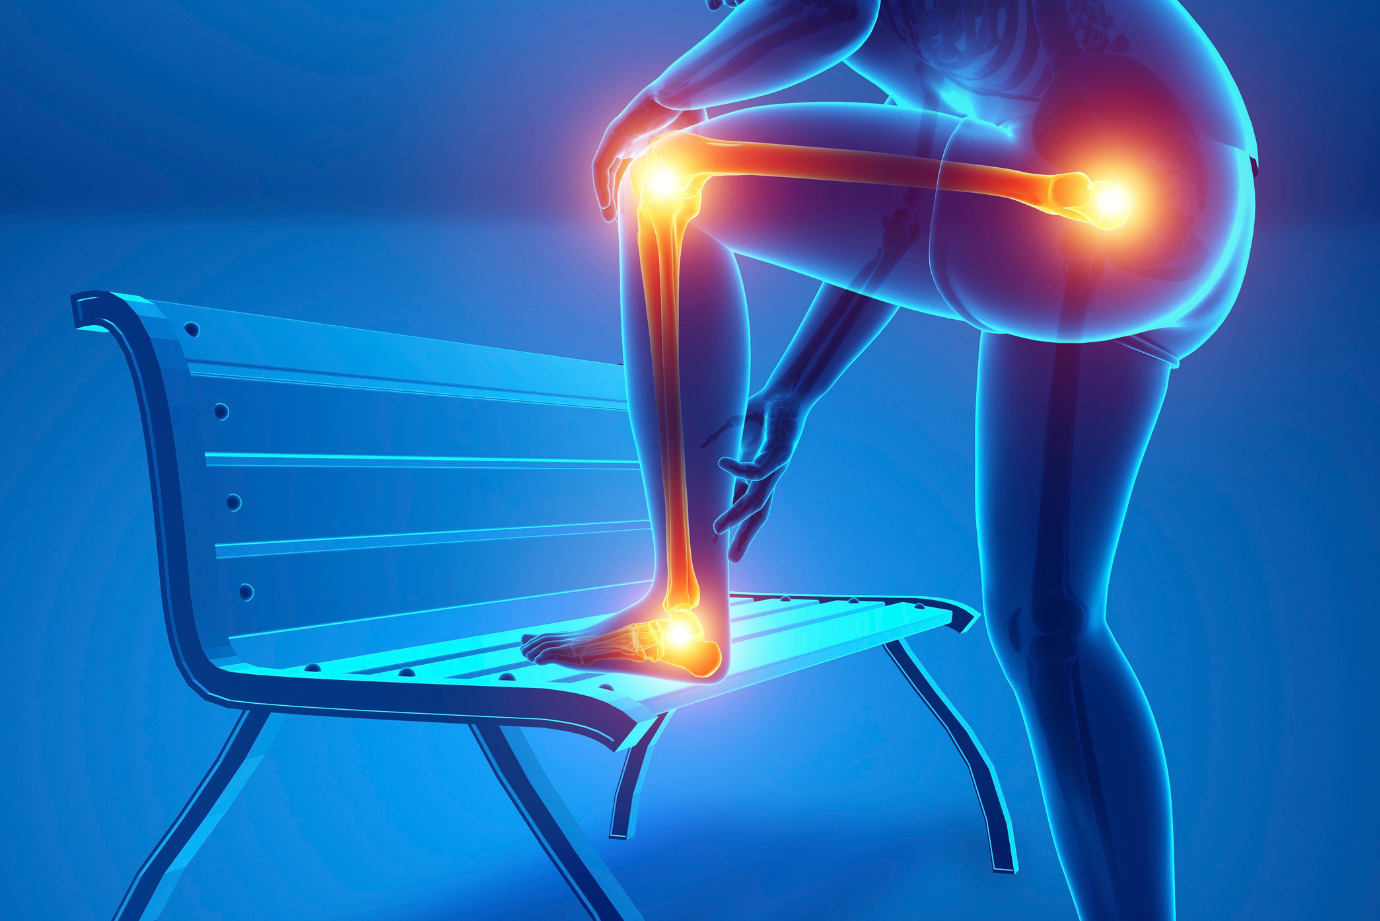

Você sente uma dor persistente na frente do joelho ao subir escadas, correr ou após longos períodos sentada? Muitas vezes,...

Você sente uma dor persistente na frente do joelho ao subir escadas, correr ou após longos períodos sentada? Muitas vezes,...